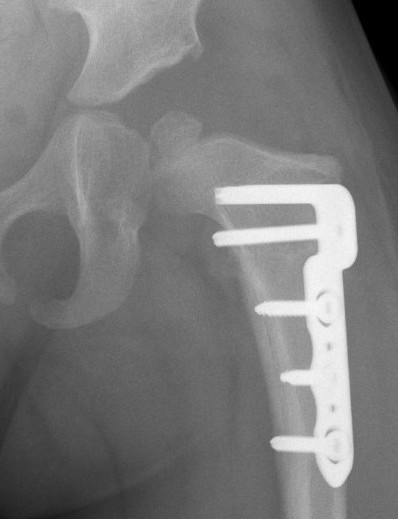

Femoral Varus Derotation Osteotomy (VDRO)

Indication

Tight reduction risking AVN

Unstable reduction with increased femoral anteversion

Increased femoral neck angle

Technique

Synthes Pediatric Proximal Femur Offset Plate Technique PDF

Youtube open reduction and VDRO video

Measure planned correction

- preoperative: 150 degrees

- postoperative: 120 degrees

Separate lateral approach

- elevate vas lateralis +/- release proximally with L shaped release

- open and protect periosteum with Homan retractors

- mark distal and proximal femur with drill holes to check rotation

- place wires up femoral neck short of physis

- use plate to mark osteotomy site

Osteotomy with microsagittal saw 1 cm below lesser tuberosity

- may need to shorten

- +/- adjust version

- apply plate and fix with screws